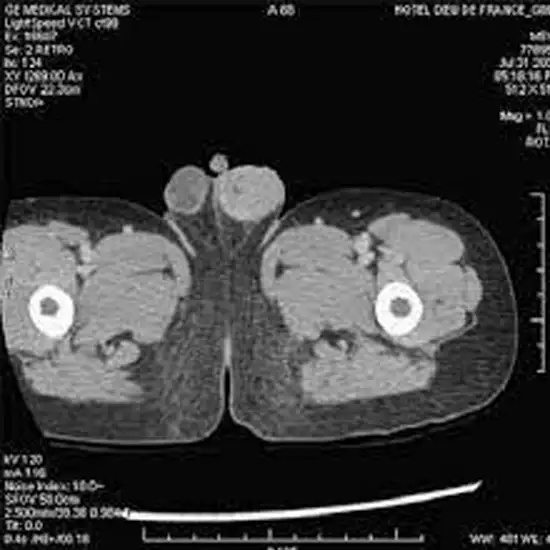

NCCT Scrotum is a plain scan of the Scrotum to visualize the internal organs and the disease condition in the Scrotum. NCCT is the short form non-contrast computed tomography, this scan does not use contrast for the scanning purpose.